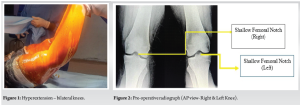

A 24-year-old young woman presented to us with the chief complaints of pain in the right knee for the past 2 years and the left knee for the past 10 months. She had difficulty in walking and climbing stairs. There was no history of injury to the knees or history suggestive of an inflammatory pathology, which ruled out the two most common reasons for musculoskeletal pain in young adults. She did not report the presence of any constitutional symptoms as well. We performed a physical examination of both knees. The knees appeared normal in inspection, and there were no associated skin changes. There was no joint line tenderness. The range of motion in both knees was −20–120°. There was 20° hyperextension in both knees (Fig. 1).

Suspecting an ACL tear in both knees, we ordered radiographs of the knees. Apart from a shallow intercondylar notch, the radiographs appeared grossly normal (Fig. 2). The patient had undergone magnetic resonance imaging (MRI) of her knees elsewhere. The MRI findings reported bilateral deficiency of ACL in both knees (Fig. 3). Although the physical examination and MRI findings diagnosed the case to be bilateral chronic ACL tear on both sides, the history was far from confirming a traumatic ACL tear.